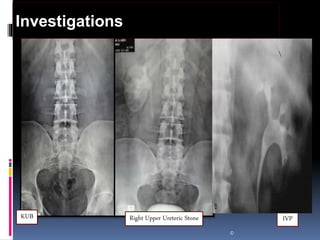

 Radiological

 KUB – 90% of Stones are Radio-opaque

 IVU: Stone appear as filling defect , obstruction & Back pressure Not useful if the

Investigations

Right Upper Ureteric StoneKUB IVP